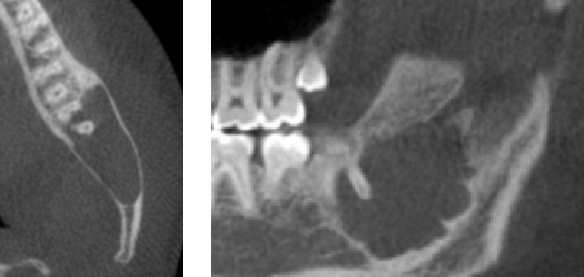

The images below are examples of pathology that have been found over the last year, usually on routine exams. Without Cone beam CT most of the pathology would go unnoticed. Patient names have been removed for privacy. Thank you for allowing the use to educate our patient base on the benefits of this imaging modality.

Case 1: Traumatic bone cyst that was successfully removed by oral surgeon.

Case 2: Dentigerous cyst around impacted wisdom tooth. Referred to surgeon.